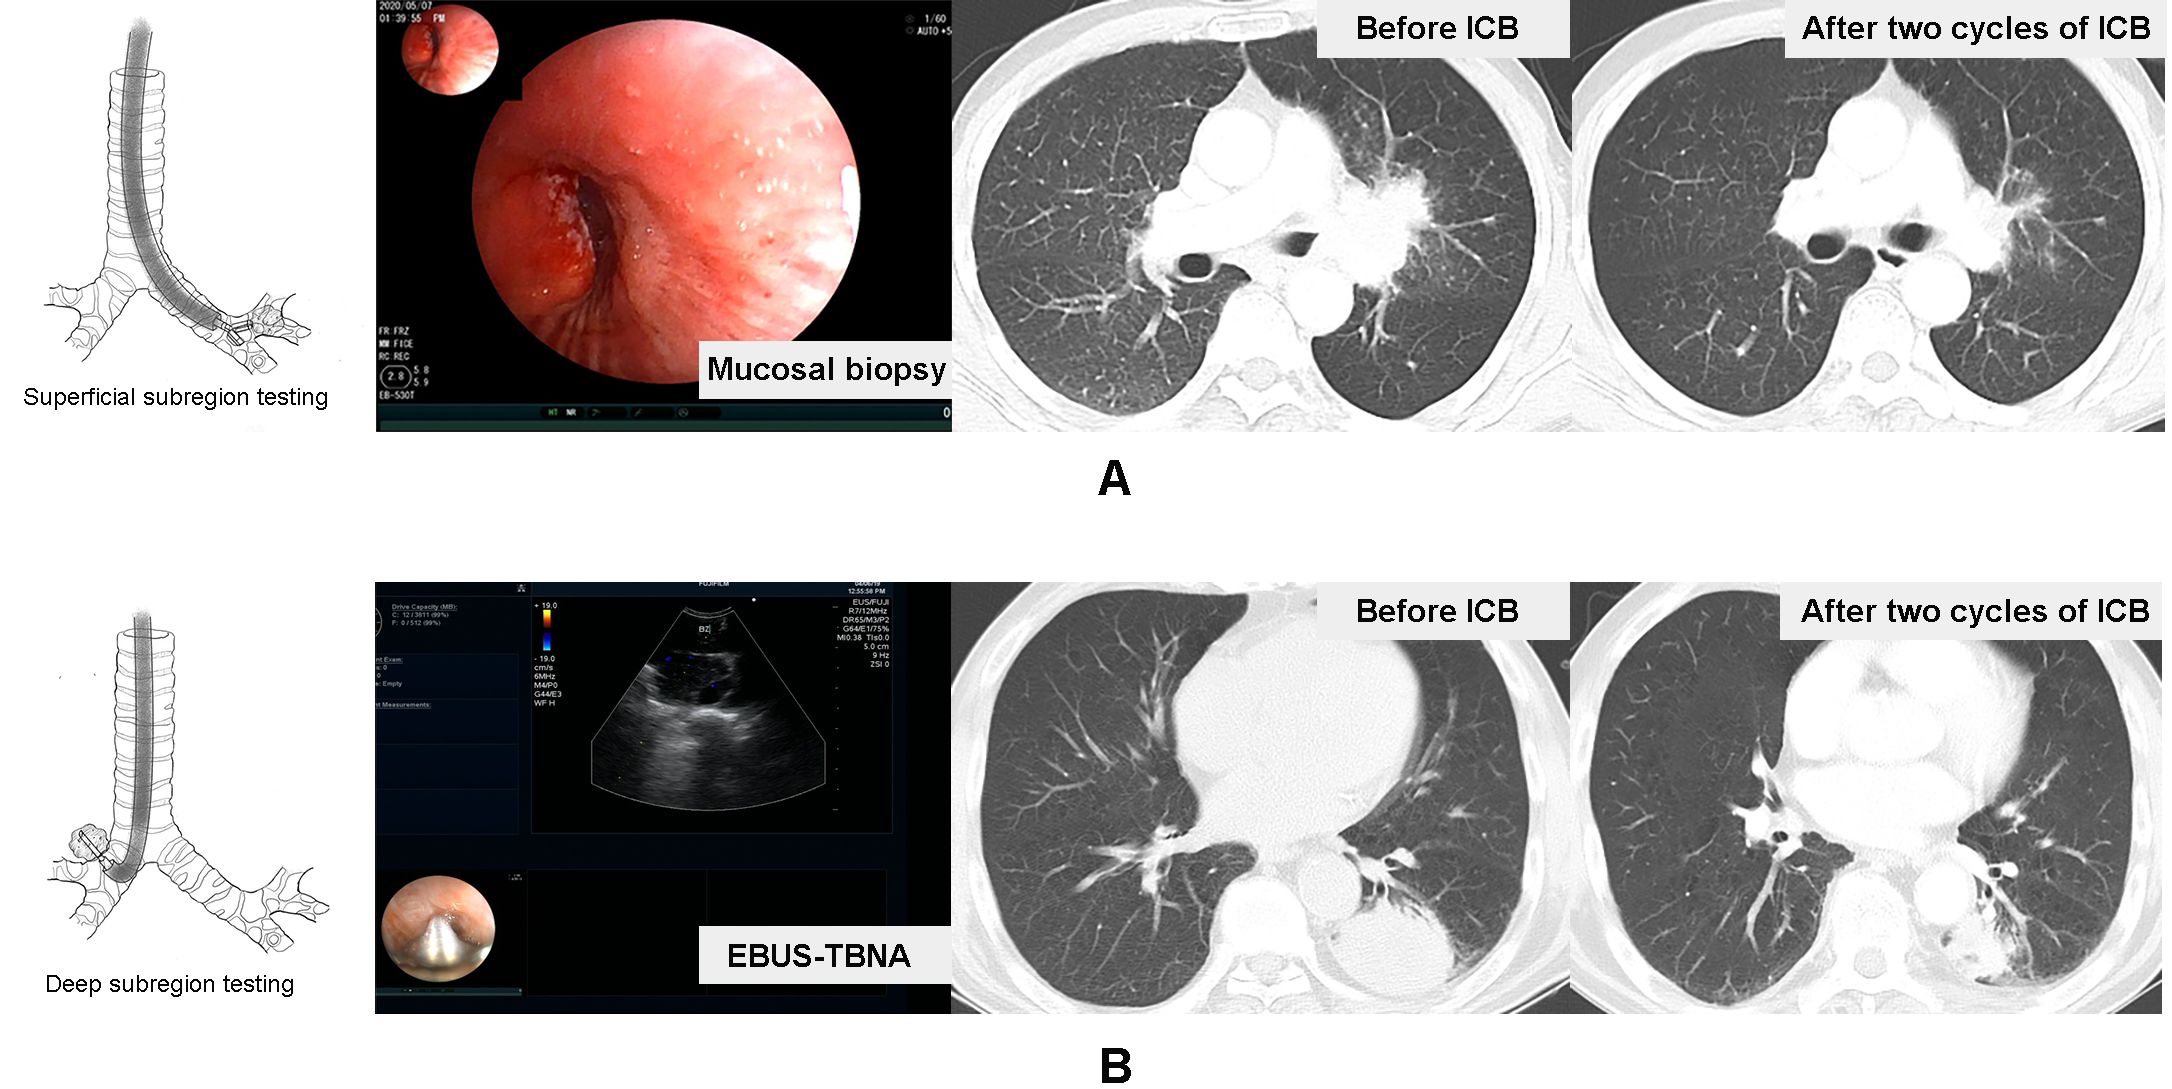

In our study, we mainly utilized endobronchial ultrasound-transbronchial needle aspiration (EBUS-TBNA) to tumor, image-guided percutaneous cutting needle biopsy (PCNB), transbronchial lung biopsy (TBLB), and transbronchial mucosal biopsy to collect sufficient samples for diagnosis, histological subtyping, and PD-L1 testing. According to the principle and basic procedures of these biopsy modalities (1618), all subjects were further divided into primary tumor superficial (PTsup) subregion-sampled cohort (TBLB, transbronchial mucosal biopsy) and primary tumor deep (PTdeep) subregion-sampled cohort (EBUS-TBNA, PCNB). Based on the accessibility of the biopsy forceps and puncture needle, the subjects were divided into two groups. The biopsy forceps could reach a depth of 2 mm, which did not extend to the center of the tumor, thus constituting the PTsup cohort. In contrast, the puncture needle could access the center of the tumor, thereby defining the PTdeep cohort. Moreover, the representative patients in these two cohorts are shown in Figure 2.

Figure 2

Diagram and imaging comparisons of lung regions are shown. In panel A, superficial subregion testing is highlighted with mucosal biopsy images and CT scans before and after two cycles of ICB. Panel B depicts deep subregion testing using EBUS-TBNA with ultrasound and corresponding CT scans before and after ICB treatment.

Figure 2. Representative patients in the tumor surface-sampled cohort and intratumor-sampled cohort. A case received mucosal biopsy of left principal bronchus to test primary tumor superficial subregion-related PD-L1 expression, and the therapeutic effect of the two-cycle ICB-based therapy was the ORR (A). Another case received EBUS-TBNA to lesion in the inferior lobe of the left lung to test the deep subregion-related PD-L1 expression, and the therapeutic effect of two-cycle ICB-based therapy was also the ORR (B).